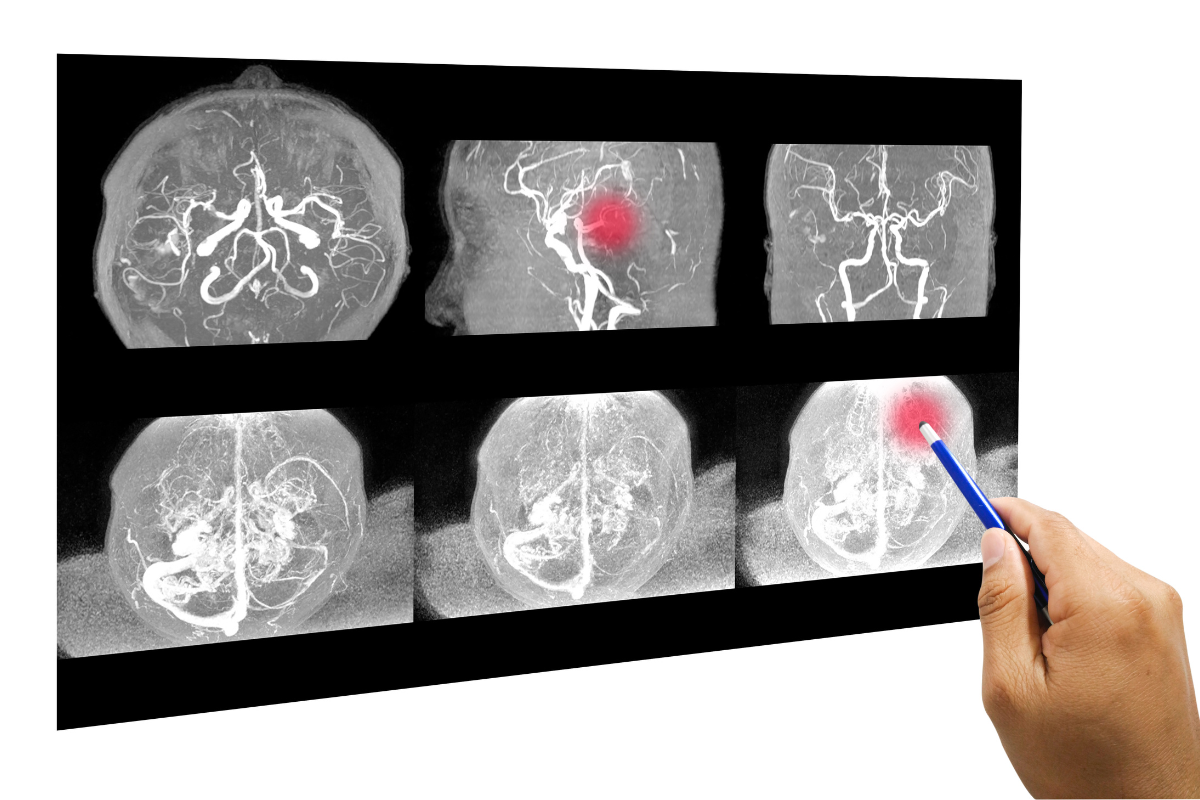

Vỡ túi phình gây xuất huyết não có thể tái xuất huyết tiếp. Ảnh: Canva

Sau khi vỡ túi phình gây xuất huyết não nó có thể tái xuất huyết tiếp, có thể gây ra tình trạng co thắt mạch máu đưa đến thiếu máu trầm trọng hơn cho mô não. Nếu túi phình vỡ vào trong khoang màng não - não (xuất huyết dưới nhện) thì máu có thể gây tắc lưu thông dịch não tủy. Điều này có thể gây ra tăng áp lực nội sọ và tổn thương mô não. Xuất huyết dưới nhện có thể gây ra mất cân bằng ion natri trong máu, xảy ra do tổn thương vùng dưới đồi (gần đáy não), việc giảm natri máu sẽ dẫn đến phù não và tổn thương não vĩnh viễn.

Túi phình mạch não dễ dàng được phát hiện khi người bệnh được chụp cắt lớp não (CT.Scan) hoặc chụp cộng hưởng từ nhân (MRI). Chụp mạch máu não ở những cơ sở y tế có trang bị máy chụp mạch máu xóa nền (DSA). Những trường hợp bị xuất huyết dưới nhện có thể được chọc dò dịch não tủy để làm xét nghiệm.